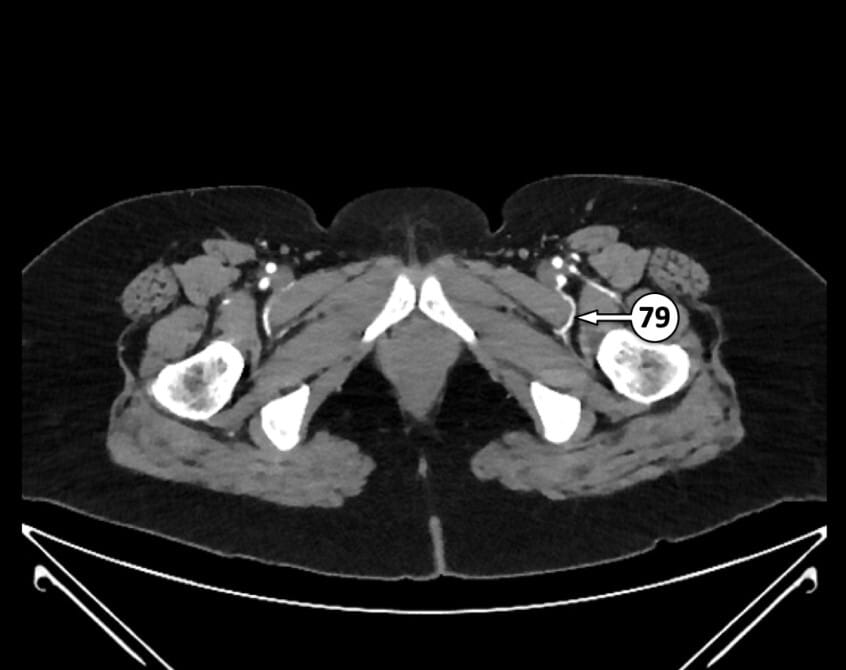

76. common femoral artery

77. internal pudendal artery in pudendal canal

78. inferior rectal artery

79. muscular perforator branch of profunda femoris artery

80. superficial femoral artery

81. profunda femoris artery